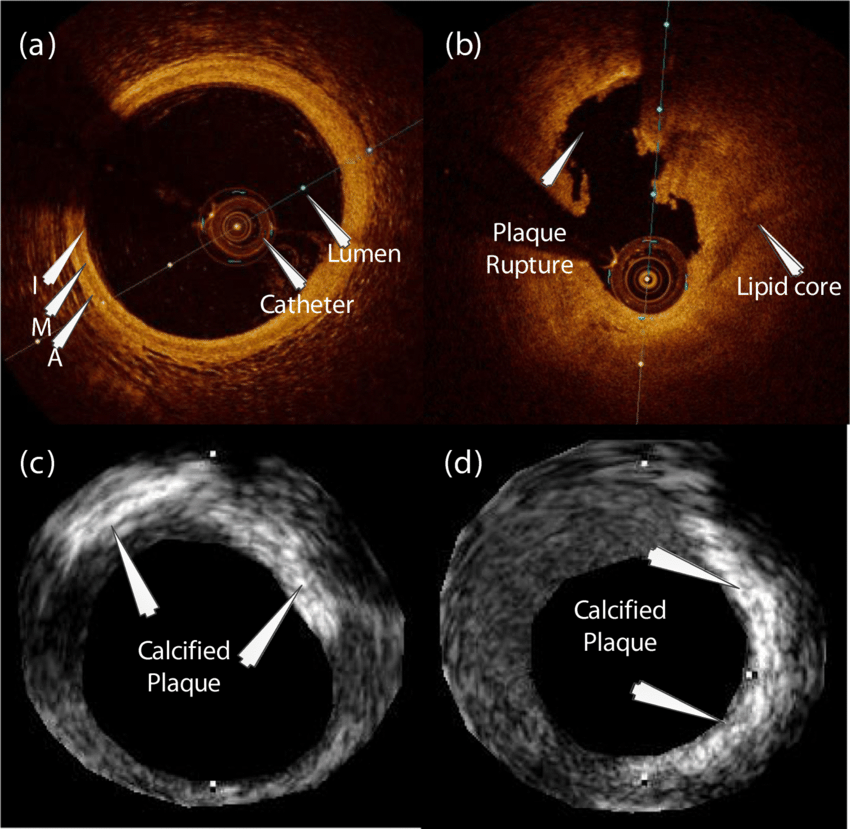

Intravascular Imaging

IVUS & OCT-guided coronary interventions